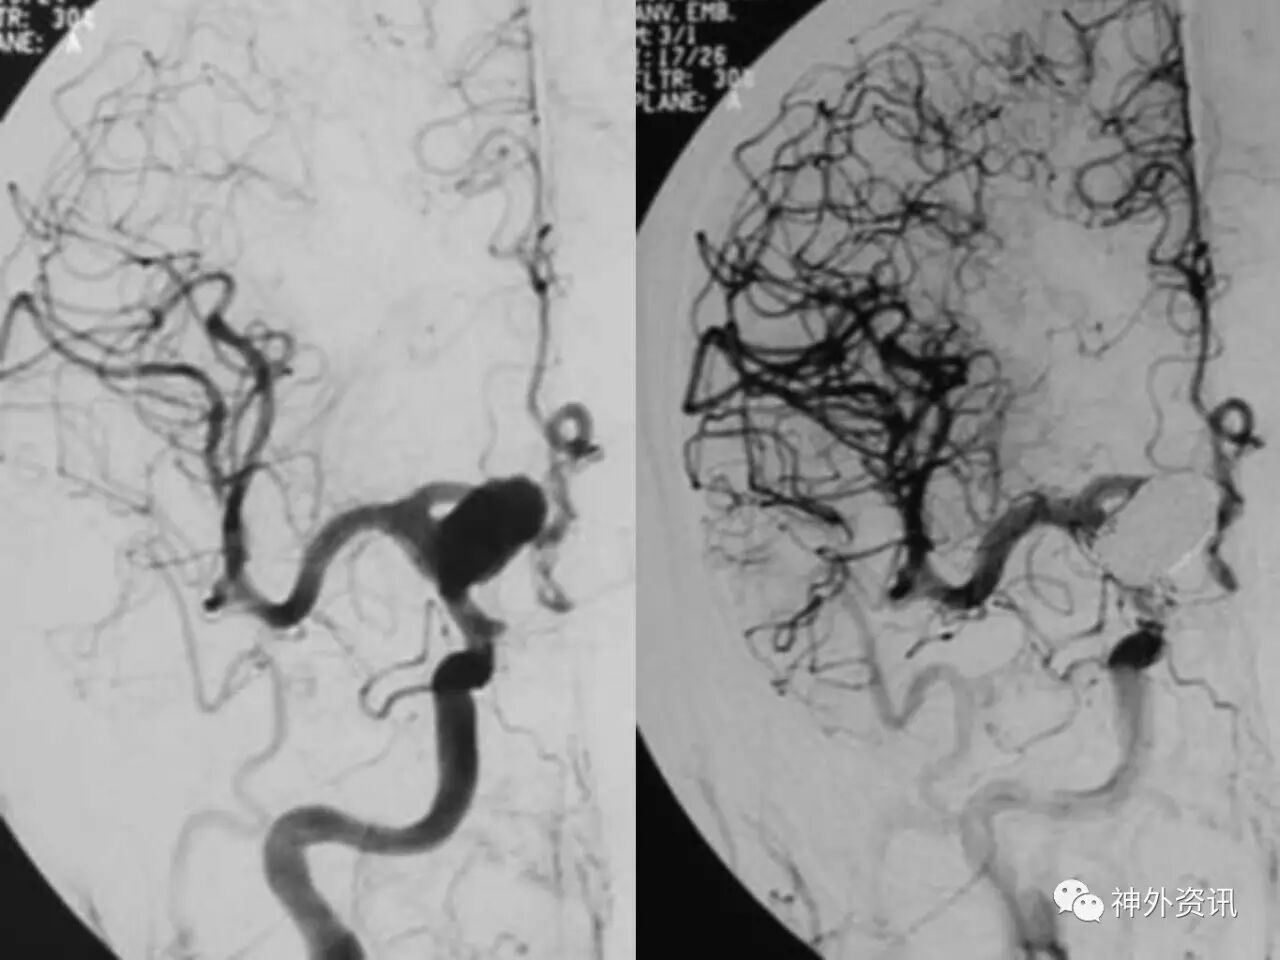

在东北地区率先开展了颈内动脉、大脑中动脉及基底动脉闭塞血管内再通、颅内动脉栓塞急性期取栓、血流导向装置治疗大型宽颈动脉瘤等,对颅内动脉瘤、动静脉畸形、颈动脉及颅内动脉狭窄、颈内动脉海绵窦瘘、硬脑膜动静脉瘘等外科治疗具有较深的造诣。完成脑血管造影8600余例,各类脑血管病介入手术共4500余例,动脉瘤、动静脉畸形、脑肿瘤、脑出血及脑外伤等外科手术1500余例。